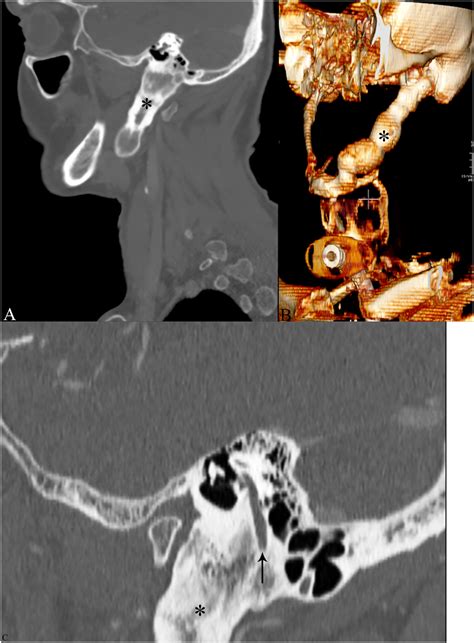

• Computed tomography (CT) scans: CT scans offer a more detailed view of the Temporal Styloid Process and can help identify fractures, elongation, or other abnormalities.

Eagle Syndrome is a rare condition characterized by an elongated Temporal Styloid Process or a calcified stylohyoid ligament. This elongation or calcification can cause compression or irritation of nearby structures, leading to a variety of symptoms, including:

Eagle Syndrome can be diagnosed through a combination of clinical examination, imaging studies, and sometimes, diagnostic injections. Treatment options may include conservative measures such as pain management and physical therapy, or surgical intervention to shorten the Temporal Styloid Process.